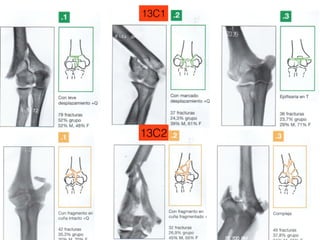

13C1

13C2